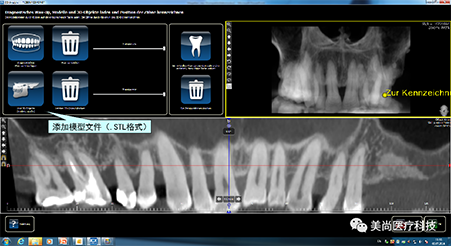

A.将CBCT数据导入软件中

C.添加模型数据

D.图像拟合

1.CT数据导入

2.成像预览

3.添加放射导板数据